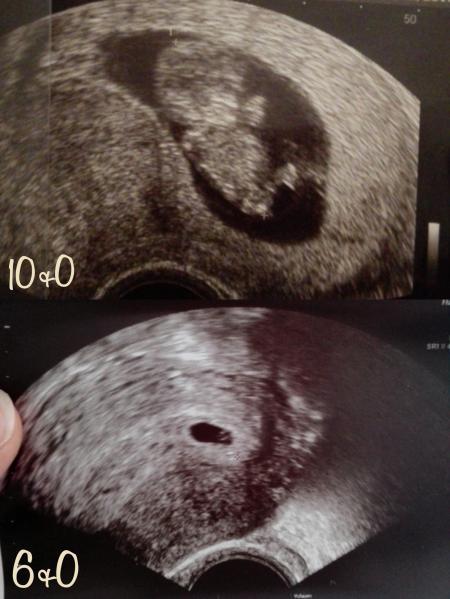

Hallo Ich war gestern zum erstemal beim Frauenarzt. Leider war ein Vertretungsarzt da und er hat sich nicht wirklich angestrengt. Ich habe nichts in der fruchthülle gesehen. Er meinte da pulsiert was, ich hab zwar es ein wenig gesehen, aber irgendwie hab ich Angst dass da nichts drin ist. Laut rechner war ich gestern 6+5, aber laut us war ich 6+0. Bei wem war das auch so?

So sah es bei mir aus also lass dich da nicht verunsichern

Bild zu

Das Bild sieht perfekt aus. So wie es in der SSW sein muss. Freu dich und verunsichere dich nicht selbst.